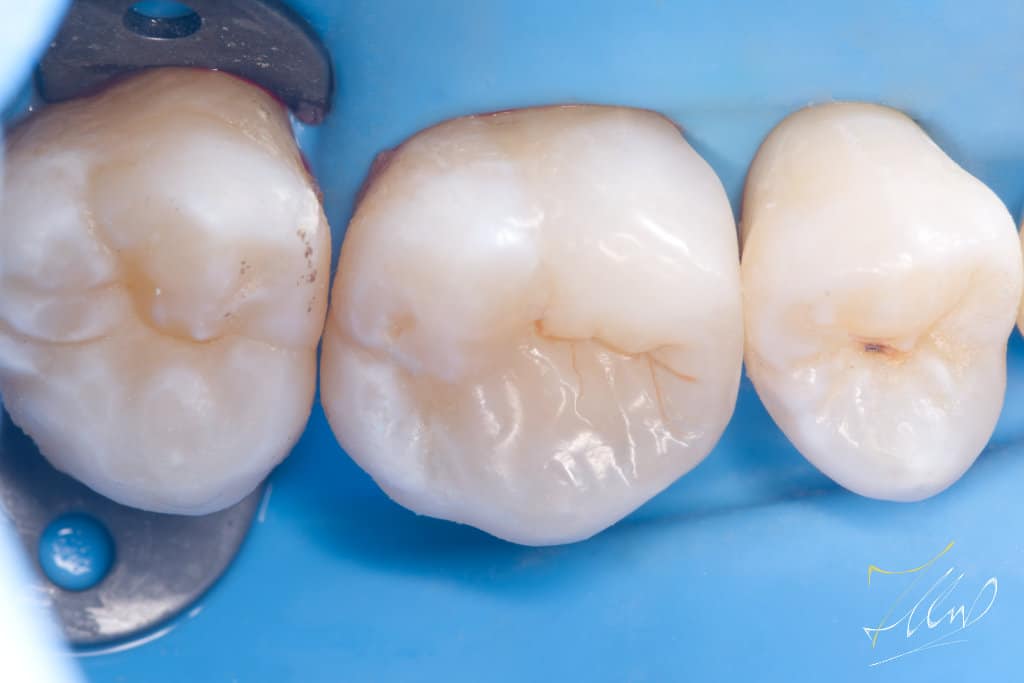

Upon initial examination, the patient reported experiencing temporary cold sensitivity and food stagnation in a specific area. The clinical diagnosis indicated that the tooth was vital, based on the Electric Pulp Test (EPT), the tooth is regarded vital, with initial response at level 36, followed by relief after 15 seconds.